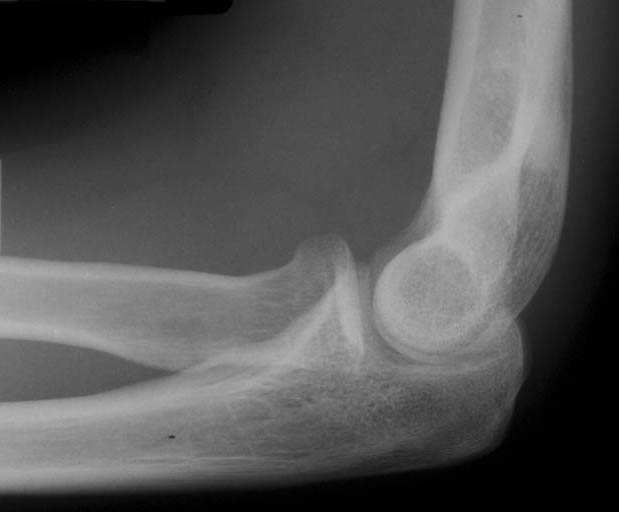

상완골 외상과염 – Nursemaid’s elbow /Pulled elbow (Nursemaid’s elbow, 보모 엘보우)

요골윤상인대(annular ligament)가 찢어져서 요골두가 일과성으로 아탈구(subluxation)된 것이며, 윤상인대의 근위부가 요골 두와 상완소두(capitellum) 사이에 끼어서 통증이 유발된다.